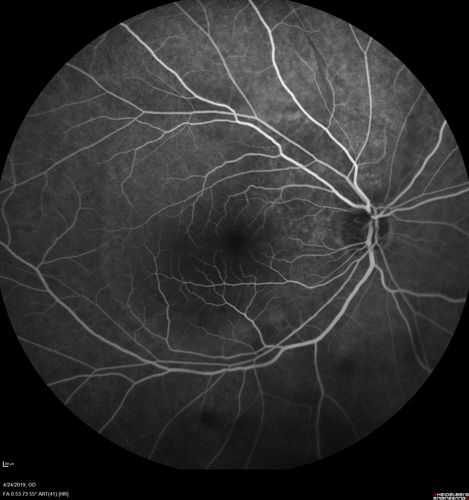

Lung Cancer Metastasis to Right Eye

63 year old female with vision loss for 6 weeks. She had been scheduled for cataract surgery and then a tumor was found. She was ultimately diagnosed with lung cancer. Vision is 20/100

Non Small Cell Lung Cancer - Metastasis to Choroid